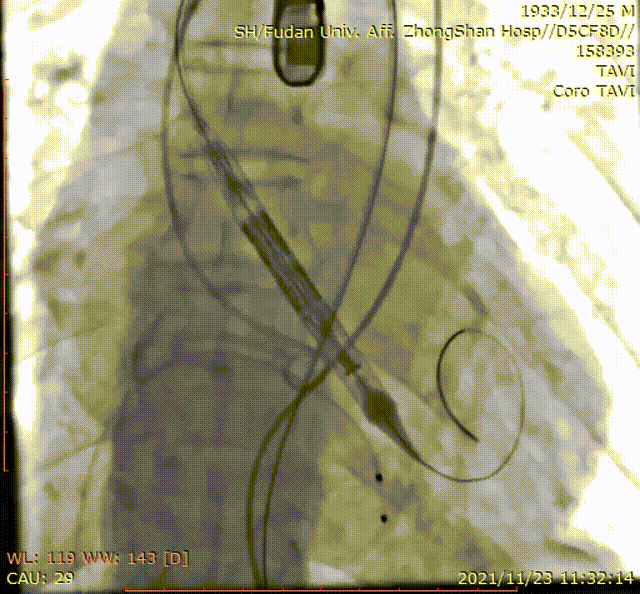

手术过程

输送系统到位

定位环释放

瓣膜精准定位